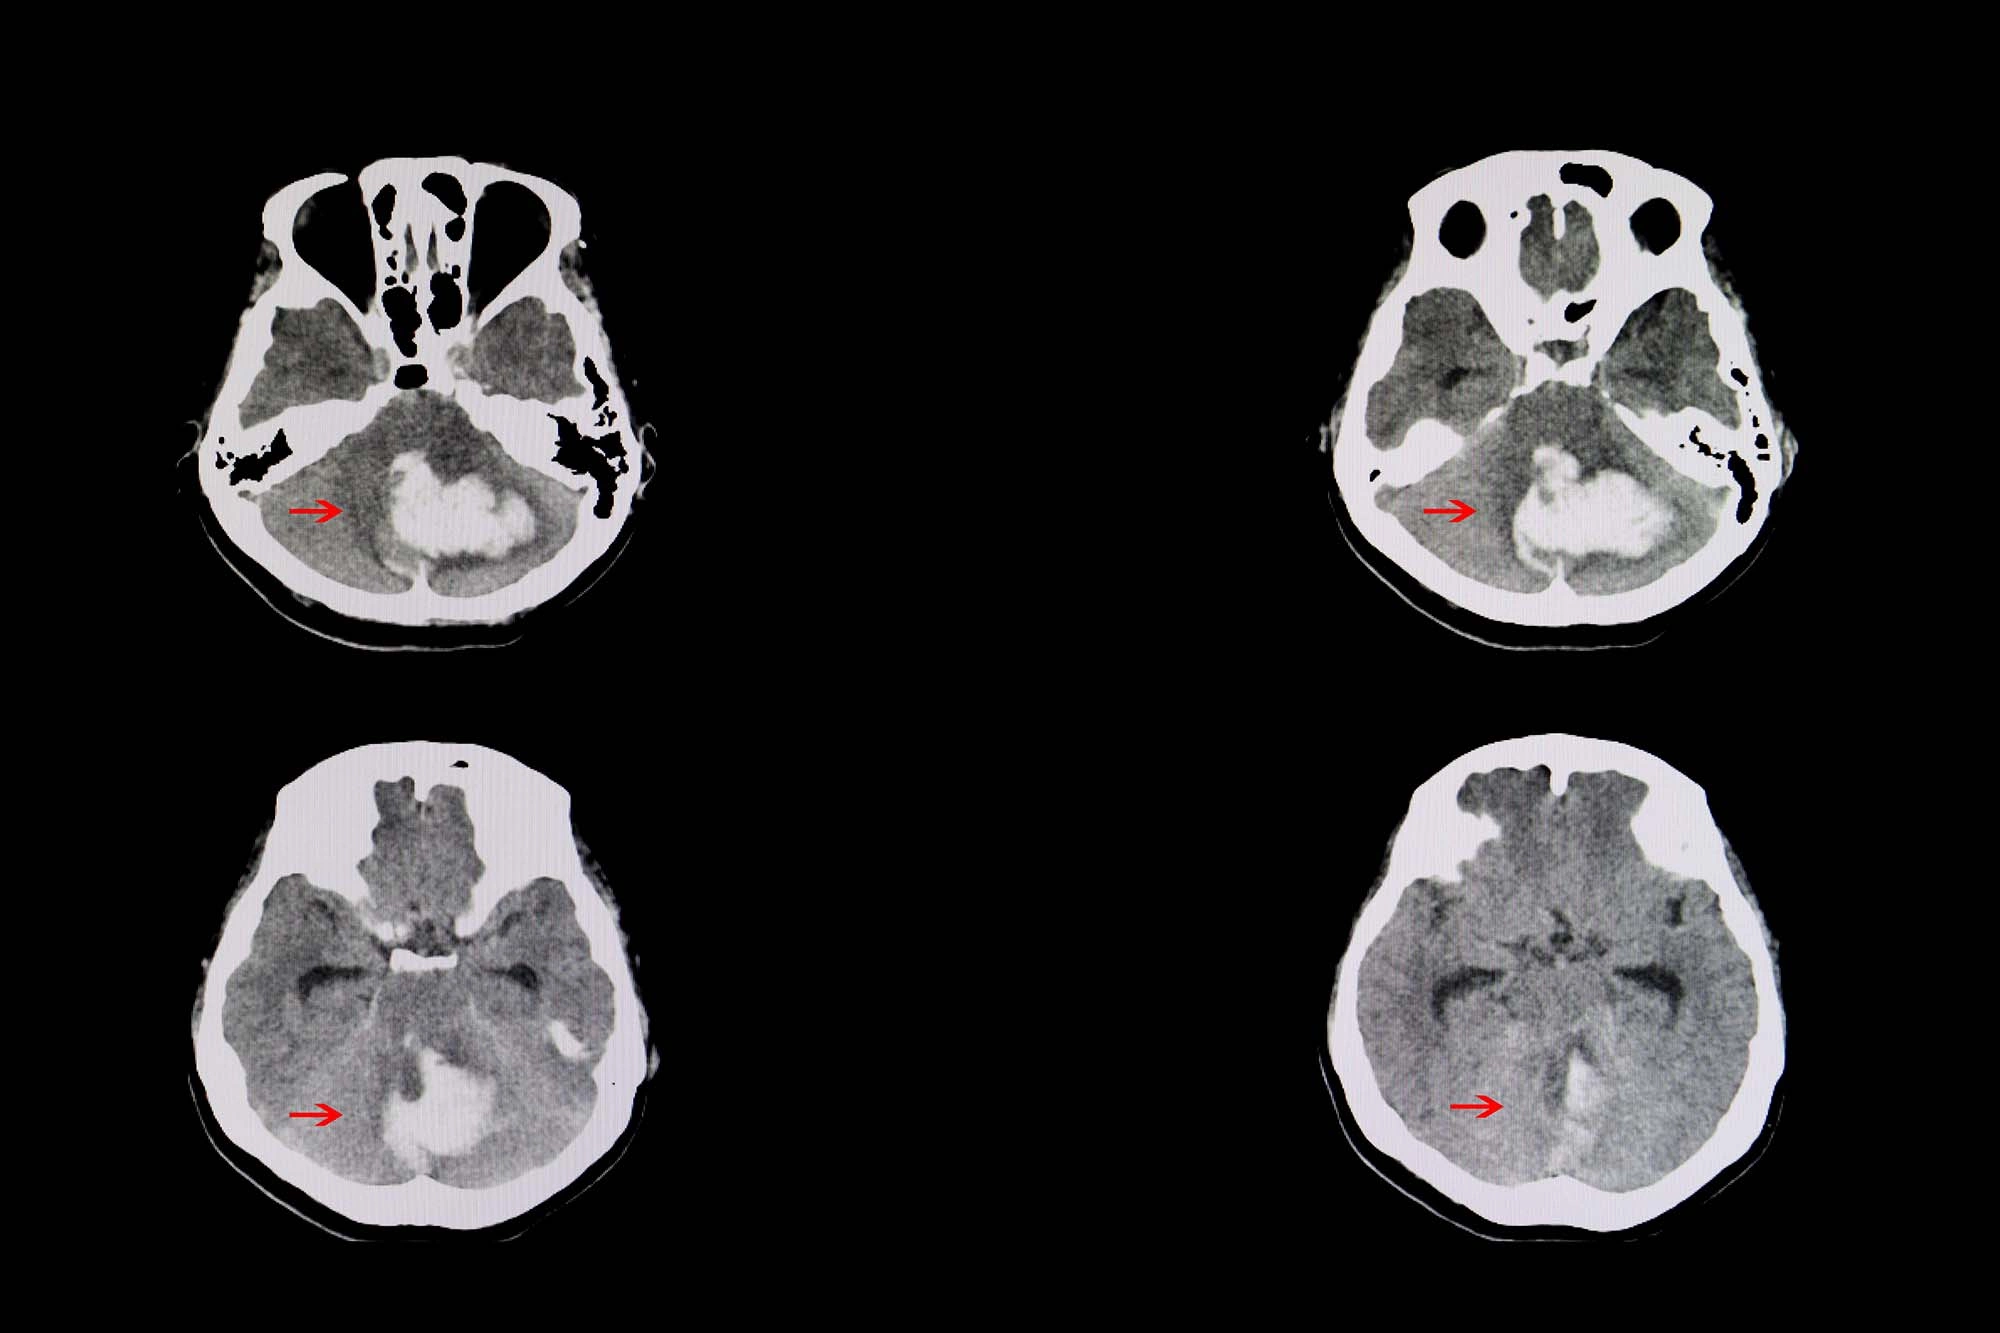

Симптомы, причины и лечение ишемического инсульта

Первые симптомы и признаки инсульта: как распознать инсульт?

Инсульт можно остановить!